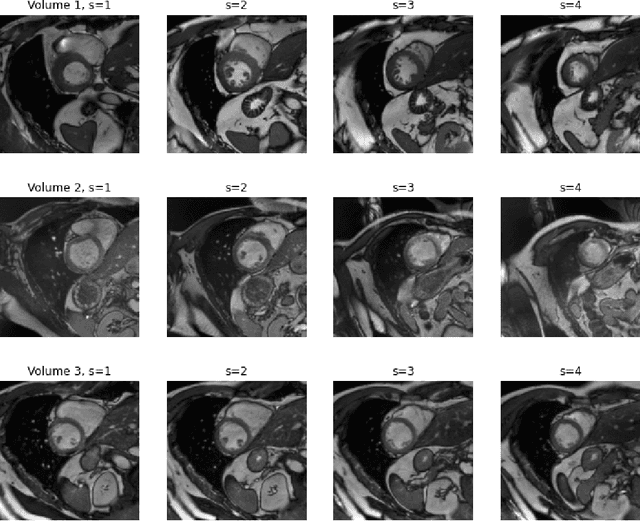

A key requirement for the success of supervised deep learning is a large labeled dataset - a condition that is difficult to meet in medical image analysis. Self-supervised learning (SSL) can help in this regard by providing a strategy to pre-train a neural network with unlabeled data, followed by fine-tuning for a downstream task with limited annotations. Contrastive learning, a particular variant of SSL, is a powerful technique for learning image-level representations. In this work, we propose strategies for extending the contrastive learning framework for segmentation of volumetric medical images in the semi-supervised setting with limited annotations, by leveraging domain-specific and problem-specific cues. Specifically, we propose (1) novel contrasting strategies that leverage structural similarity across volumetric medical images (domain-specific cue) and (2) a local version of the contrastive loss to learn distinctive representations of local regions that are useful for per-pixel segmentation (problem-specific cue). We carry out an extensive evaluation on three Magnetic Resonance Imaging (MRI) datasets. In the limited annotation setting, the proposed method yields substantial improvements compared to other self-supervision and semi-supervised learning techniques. When combined with a simple data augmentation technique, the proposed method reaches within 8% of benchmark performance using only two labeled MRI volumes for training, corresponding to only 4% (for ACDC) of the training data used to train the benchmark.